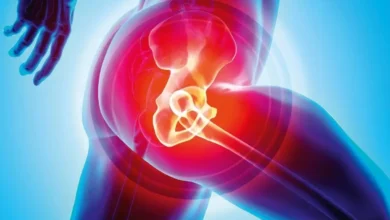

۱۰. آناتومی تاندون آشیل

- تاندون آشیل اتصال مارپیچیشکلی به پاشنه دارد.

- تمرین حرکات چرخشی مچ پا (مثلاً پرونیشین/سوپینیشن، اینورژن/ایورژن – حرکات بردن پا به داخل و بیرون) به بارگذاری فیبرهایی که در جهات مختلف قرار دارند، کمک میکند.

- این ساختار مارپیچ ممکن است در مورد سایر تاندونها نیز صدق کند.